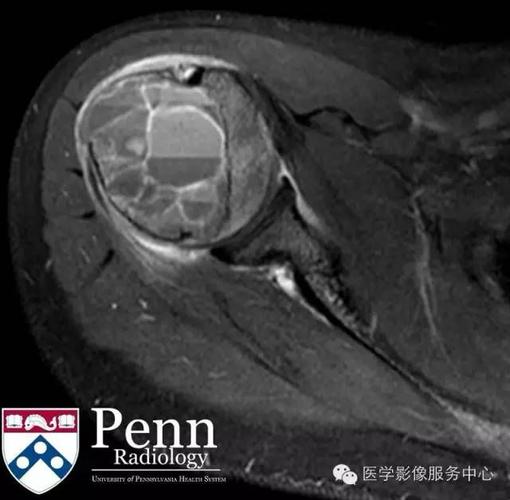

动脉瘤样骨囊肿(abc)

动脉瘤样骨囊肿影像

动脉瘤样骨囊肿图片

动脉瘤样骨囊肿ct表现

胫骨动脉瘤样骨囊肿